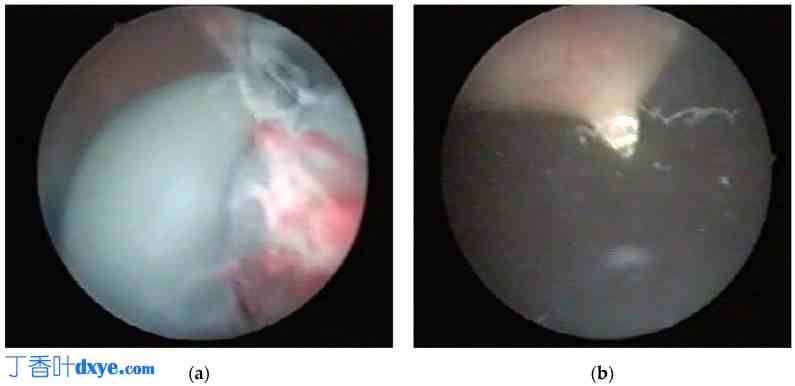

对于病例 1,在硬膜外麻醉下进行了内窥镜检查。使用 16 Ch 膀胱镜与电缆一起插入膀胱进行膀胱镜检查,未发现任何病变或膀胱穿孔。在膀胱内部,观察到电缆在膀胱颈处有一个结和一个大环(图 4a)。在膀胱镜引导下,将 10 毫米腹腔镜套管针经皮插入耻骨上水平的膀胱(图 4b)。将一把剪刀穿过套管针,可在环和结处切断电缆(图 5)。然后在内窥镜引导下通过腹腔镜套管针取出碎片。取出套管针后插入 18 Fr 膀胱导管,完成手术。

图 4。

4.jpg

病例 1 — 膀胱镜视图:(a) 膀胱颈处有结节;(b) 在膀胱镜引导下,将 10 毫米腹腔镜套管针经耻骨上插入膀胱。

图 5。

5.jpg

病例 1 — 膀胱镜视图:(a、b)。使用插入腹腔镜套管针的剪刀剪断电缆环。